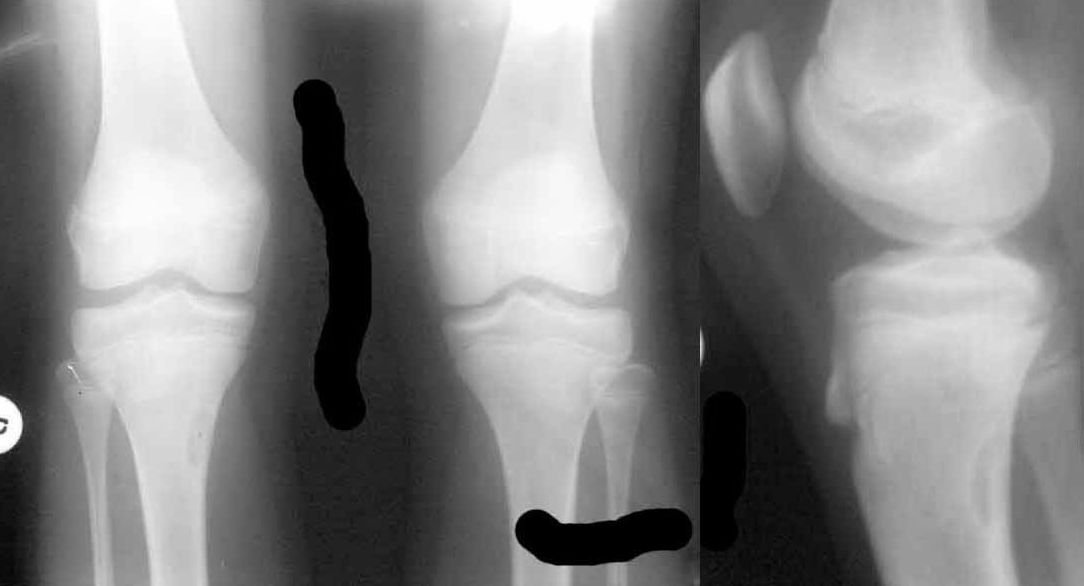

Коллеги, обратились педиатры с вопросом:"Девочке сейчас 12.5 лет. Летом этого года стартовал пубертат, начала вытягиваться.

В течение лета были активные физические нагрузки, в августе - длительные пешие походы в горах. С сентября стали появляться боли в коленных суставах, связанные с подъемом по лестнице и при приседании. Боли непостоянные, то в одной, то в другой ноге, иногда одновременно в обоих коленях. В покое и при обычной ходьбе боли не отмечаются. 18.01.2011 сделали снимки коленных суставов - выявлен очаг фиброза в правой большеберцовой кости?"

Вариант фиброзной дисплазии (фиброзный кортикальный дефект). В плане обследования КТ. В плане лечения - наблюдение, Ro-гр. раз в полгода. Если не увеличивается в размерах оставить в покое.

Согласен с Алексеем. Фиброзный метафизарный кортикальный дефект - особенность формирования костей в местах крепления сухожилий наиболее активных мышц, клинически не проявляется, выявляется у 15% здоровых подростков, занимающихся спортом. самостоятельно замещается нормальной косчтной тканью после окончания полового созревания, оперативного лечения не требует. С уважением, врач-рентгенолог УНИИТО, Зельский И.А.

Osgood-Schlatter est', esho imeetsya kista bolshebertsovoy kosti po medial'noy poverkhnosti, vidna na obeikh proektsiakh.

на данных снимках не очень хорошего качества сканирования можно думать об очаге фиброзной дисплазии. Данное место наиболее частое для подобных образований, мне неоднократно доводилось оперировать эту патологию- экономная резекция с замещением дефекта Коллапаном. Можно сделать несколько снимков в косых проекциях и, если доступно, МРТ, КТ даст слишком большую дозу ребенку.

Сама патология неопасна, но есть данные о том, что злые опухоли чаще растут из подобных очагов,чем из здоровых костных клеток.

1. У Вашей пациентке метафизарный фиброзный дефект проксимального отдела большеберцовой кости. Локализуются данные образования в местах прикрепления активных групп мышц, связаны могут быть с повышенными физическими нарузками (как в Вашем случае). При данной клинике и рентгенологической картине необходим разгрузочный режим (исключить бег, прыжки) и наблюдение. В настоящий момент угрозы патологического перелома нет, поэтому более оправдана консервативная тактика.

2. О болезни Осгуда-Шлаттера (были предположения в комментариях) нельзя судить только по рентгенологической картине, тем более что она соответствует норме - нет изменений структуры, отсутствует фрагментация. Остеохондропатии в данном случае без клиники быть не может.

Это вариант фиброзной остеодисплазии- экстакортикальная неоосифицирующая фиброма проксимального отдела б/берцовой кости. Течение , как правило благоприятное , наблюдайте и всё будет ОК!

Фиброзная дисплазия (кортикальный дефект). Скорее всего случайная находка. Тактика:если дефект более 1/3 диаметра б\б кости - оперировать (риск возникновения перелома), если менее - нет. В данном случае - наблюдать (а можно и не наблюдать, оставить в покое). Боли связаны с чем-то другим (скорее всего перегрузки - на месяц-другой освободить от тренировок).